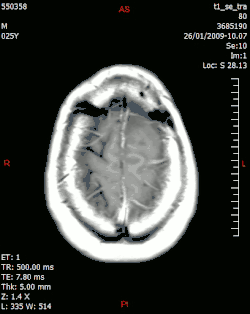

МРТ, визуализация композитными изображениями мультиформной глиобластомы

Физика медицинской визуализации также известна как физика диагностической и интервенционной радиологии. Клинические (как «штатные», так и «консультирующие») физики[14] обычно занимаются областями тестирования, оптимизации и обеспечения качества таких областей физики диагностической радиологии, как рентгенография, рентгеноскопия, маммография, ангиография и компьютерная томография. , а также методы неионизирующего излучения, такие как УЗИ и МРТ. Они также могут заниматься вопросами радиационной защиты, такими как дозиметрия (для персонала и пациентов). Кроме того, многие физики-визуалисты часто также связаны с системами ядерной медицины, включая однофотонную эмиссионную компьютерную томографию (ОФЭКТ) и позитронно-эмиссионную томографию (ПЭТ). Иногда физики-визуалисты могут заниматься клиническими областями, но в исследовательских и учебных целях[15], например, для количественной оценки внутрисосудистого ультразвука как возможного метода визуализации конкретного сосудистого объекта. В некоторых случаях для научных исследований и диагностики структур и функций на микро- нано-уровне целесообразно использование электронной микроскопии[16][17].